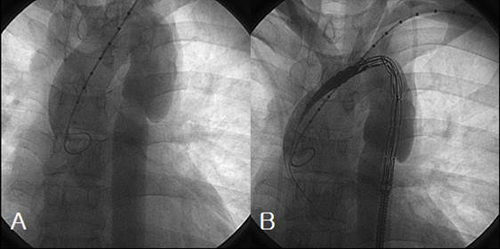

Sudden disruption of the aortic isthmus (A).Successful repair of a blunt aortic injury can be accomplished using endolumi- COVER STORY The Gore TAG thoracic device should not be oversized more than 18% based on the aortic diameter, as indicated by the ... Get Doc